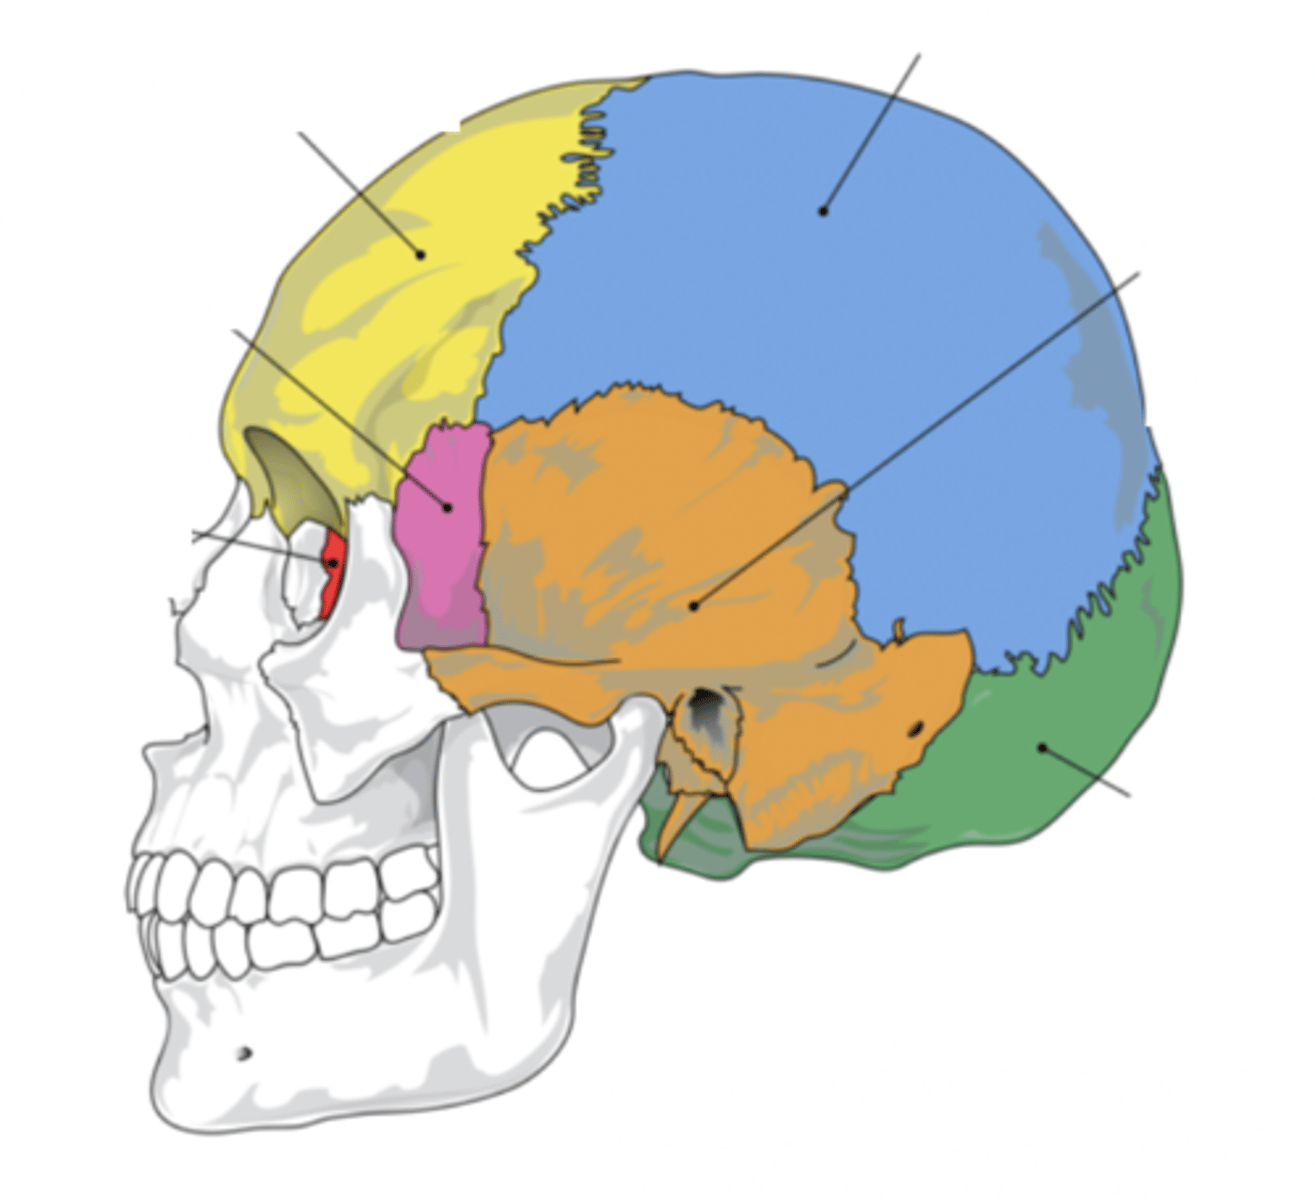

Cranial Bones (8)

- Ethmoid

- Frontal

- Sphenoid

- Temporal (2)

- Occipital

- Parietal (2)

(EFSTOP)

Ethmoid Bone

Forms part of the posterior portion of the nose, the orbit, and the floor of the cranium (red)

Frontal Bone

Bone that forms the forehead (yellow)

Sphenoid Bone

Forms part of the base of the skull and parts of the floor and sides of the orbit (pink)

Temporal Bone (2)

Bone that forms parts of the side of the skull and floor of the cranial activity (orange)

Occipital Bone

Bone that forms the back of the head (green)

Parietal Bone (2)

Either of two skull bones between the frontal and occipital bones and forming the top and sides of the cranium (blue)

4 Main Sutures of the Skull

- Saggital

- Lamboid

- Coronal

- Squamous

(SLCS)

Saggital Suture

Suture that separates the left and right parietal bone

Lamboid Suture

Suture between the occipital and parietal bones

Coronal Suture

Suture between the parietal and frontal bones of the skull

Squamous Suture

Suture between parietal and temporal bones